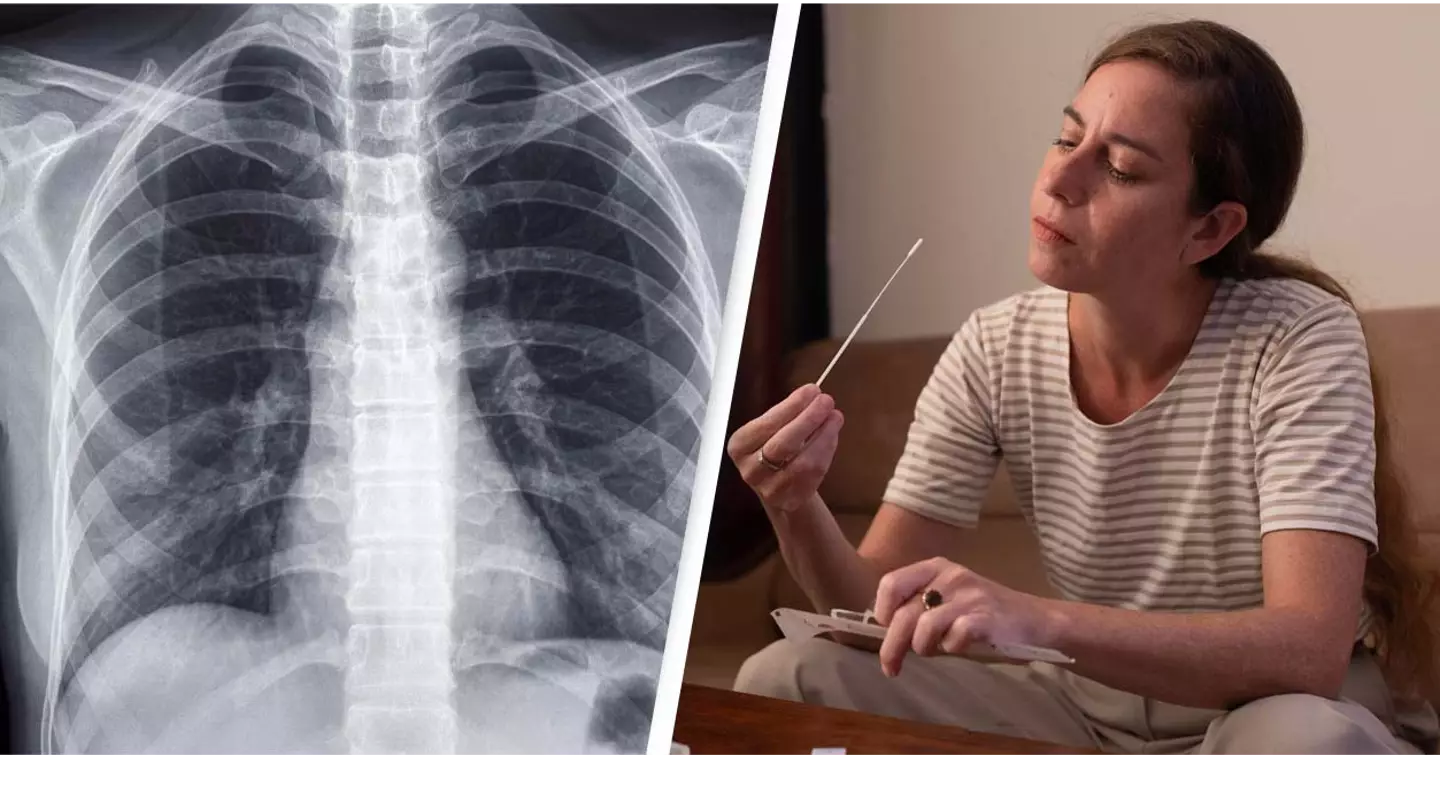

A study has suggested that some people who suffer from long coronavirus could have hidden lung damage.

An NIHR funded team of scientists from Oxford, Sheffield, Cardiff and Manchester conducted a small pilot study which examined the lungs of 11 people suffering from long Covid symptoms, using a novel xenon gas scan.

The scan is used to detect any abnormalities within the lungs which cannot be picked up by routine scans such as X-rays and CT scans.